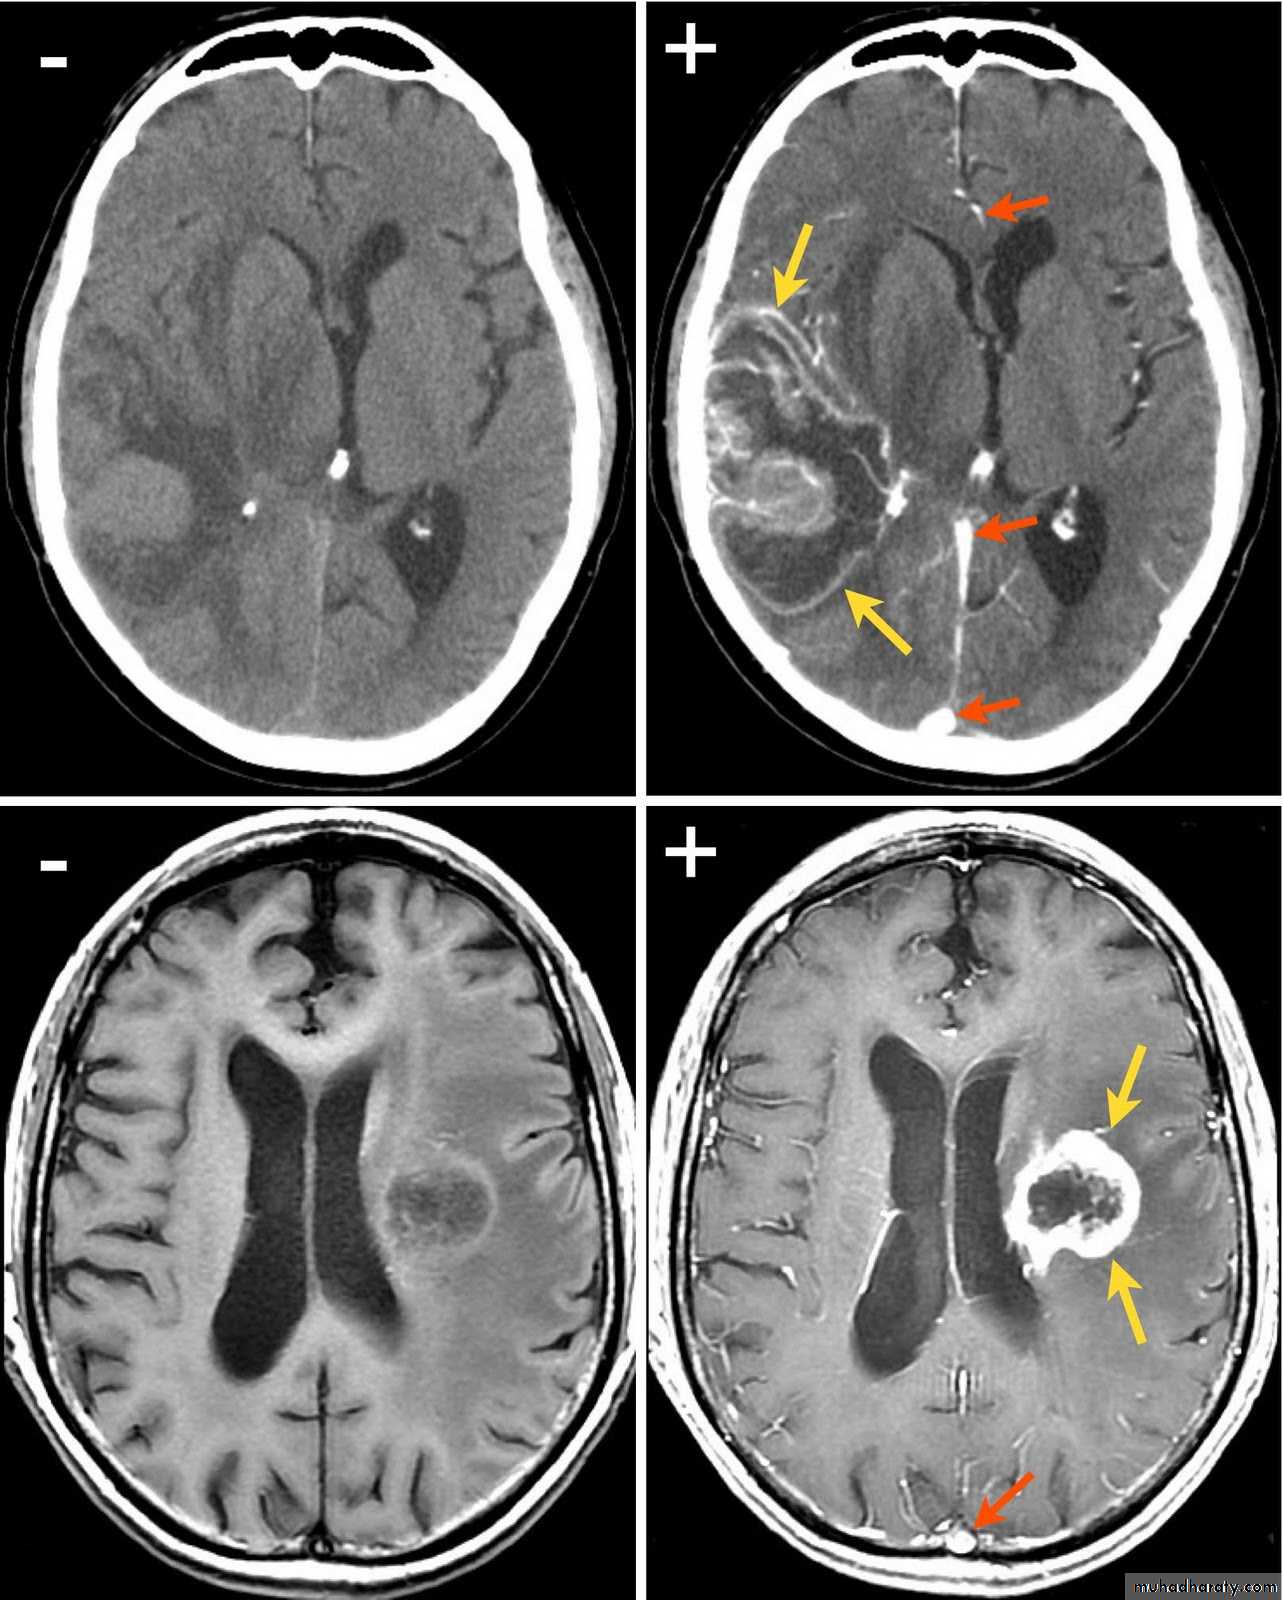

Secondary metastasis

Old age group above 50 Y , any lesion within the cerebellar hemisphere it is secondary metastasis unless proven otherwise F. from breast CA M. from bronchogenic CA .

Appear as nodular single or multiple lesion hypo dense or hyper dense .

Surrounded by per focal edema

Enhanced as solid or ring pattern of enhancement .